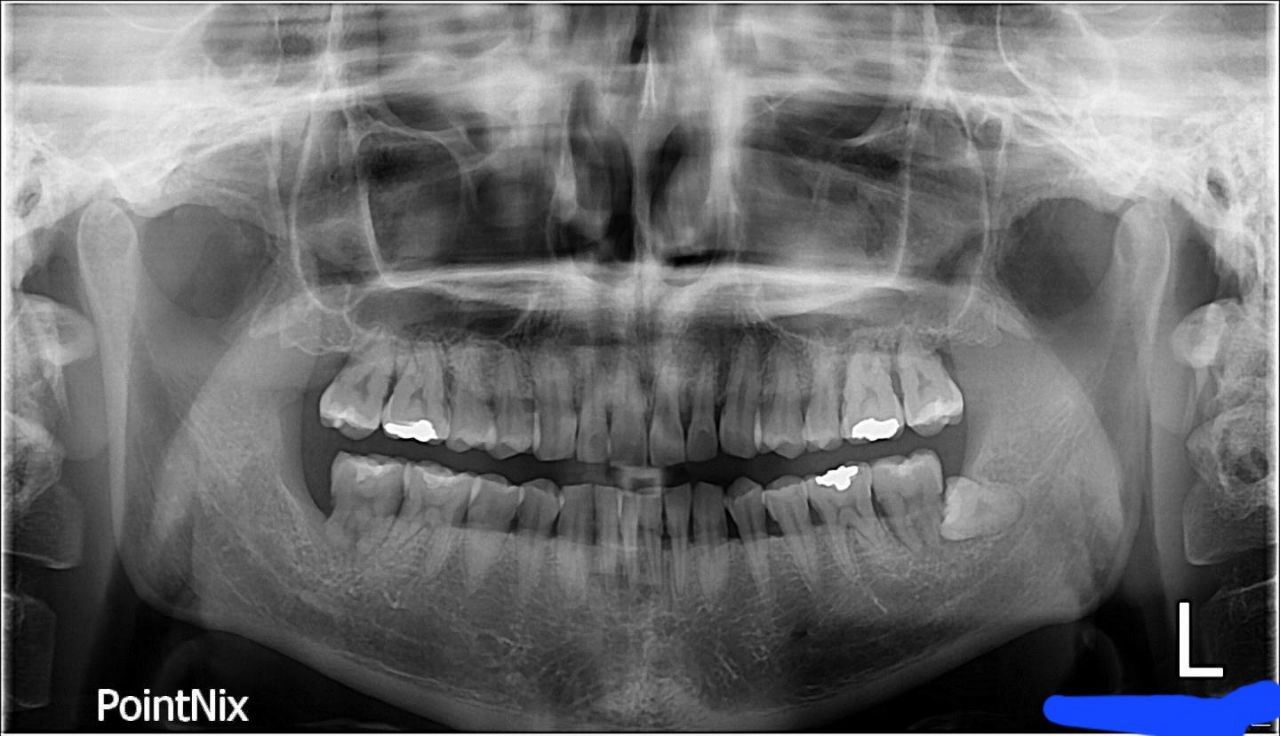

엑스레이를 찍어보니 치주질환이 심해지면서 왼쪽 어금니 뼈가 녹아 상악동 거상술과 임플란트를 해야 한다는 말을 들었습니다.

처음 통증을 느끼고 찍은 엑스레이 사진입니다.